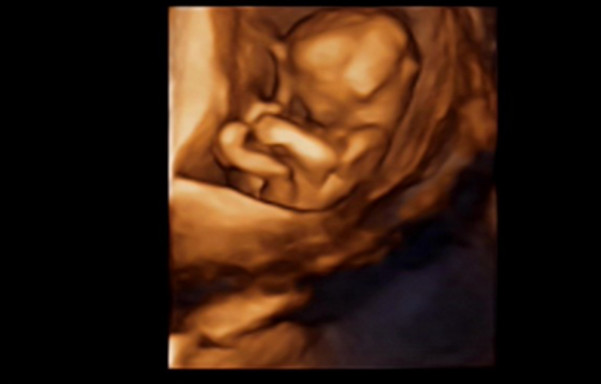

27岁的曹女士,已经怀孕六个月了。三天前,“孕味十足”的她,在丈夫的陪同下来到医院,准备进行提前预约好的四维彩超检查。但是万万没想到,检查结果让她的心情一下跌入低谷!通过影像显示,胎儿嘴唇中间竟然有一指宽的裂痕。经过医生再次仔细确认,腹中的胎儿确实患有唇腭裂,也就是“兔唇儿”。

唇腭裂患儿,是因为牙槽突间骨组织的缺失,造成上颌牙弓的完整性丧失,鼻基底部塌陷,牙槽突裂隙部恒尖牙萌出受阻。胎儿出生以后,需要通过牙槽突植骨术来完成唇部整形。手术具体怎么做,什么时候做,要做几次,这些都要根据孩子的具体病情。至于是否要生出来,这个就要由孕妇及家人自己决定。